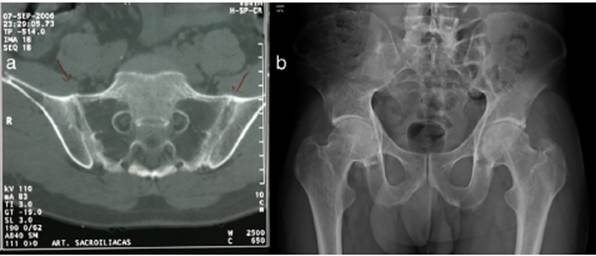

Al examen físico se encuentra el paciente con placas eritematosas, circunscritas con bordes elevados y descamación gruesa que comprometen toda la superficie corporal (figs. 1a y 2a). En el cuero cabelludo, placas con descamación adherente, tipo falsa tiña amiantácea, extendiéndose más allá del borde de implantación anterior del pelo. En algunas uñas se observa onicólisis, hiperqueratosis subungular y signo de la gota de aceite (fig. 3a). Se realiza biopsia de piel en la cual se evidencia paraqueratosis y pústulas intracórneas (fig. 4), hallazgos compatibles con psoriasis. Se calcula un PASI (siglas en inglés para índice de severidad de psoriasis según área) de 48. Con estos nuevos hallazgos, se realizan estudios imagenológicos, encontrando en radiografía de manos osteopenia difusa de los huesos del carpo derecho con disminución de espacios articulares interfalángicos proximales del dedo 5 en forma bilateral y del dedo 3 de la mano derecha con mínimo edema de tejidos blandos, en radiografía de columna cervical fusión de las articulaciones facetarias C7 a T1 y, en los pies, subluxación metacarpofalángica de todos los dedos y deformidad en valgo (fig. 5a). La tomografía axial computarizada de las articulaciones sacroilíacas muestra fusión de los 2/3 inferiores y esclerosis de 1/3 superior (fig. 6a).

Figura 6 a) Tomografía computarizada de articulaciones sacroilíacas, corte axial: fusión de las articulaciones sacroilíacasen los 2/3 inferiores por anquilosis bilateral y esclerosis de 1/3 superior bilateral. b) Radiografía de cadera, proyecciónanteroposterior: fusión completa de las articulaciones sacroilíacas, las relaciones articulares coxofemorales y en la sínfisisdel pubis están preservadas, densidad ósea disminuida.

Es evaluado por reumatología quienes descartan artritis reumatoide y consideran que puede presentar una artritis psoriásica con componente mixto: sacroilitis y poliartritis simétrica, debido a la presencia de compromiso temprano de articulaciones sacroilíacas para la primera y posteriormente compromiso cervical, manos, rodillas y pies para la segunda. Se realizan VDRL, ELISA para VIH, anticuerpos para hepatitis B, y ANA los cuales son negativos, y perfil hepático y perfil renal los cuales son normales, relación albúmina/globulinas de 0,4 compatible con desnutrición. Con lo anterior se inicia manejo con metotrexate (MTX) 15 mg/semana. Tres meses después, en control por consulta externa, se encuentra paciente con ligera mejoría por lo cual se aumenta dosis de MTX a 20 mg/semana. Un mes después se considera paciente candidato para manejo con biológico dada la persistencia de la sintomatología articular y lesiones en piel. Se solicita PPD la cual es negativa (0) y se inicia tratamiento con infliximab 200 mg/semana 0, 2, 6 y luego cada 8 semanas junto con MTX 15 mg/semana. Dos meses después se evidencia mejoría de lesiones en piel, disminución de dolores articulares y gran mejoría en los arcos de movimiento de articulaciones permitiendo que el paciente volviera a caminar. Un año después se encuentra reactivación de la enfermedad cutánea por lo cual se aumenta dosis de infliximab a 300mg/8 semanas y se reduce dosis de MTX a 12,5 mg/semana. Desde entonces se ha disminuido la dosis de MTX progresivamente hasta alcanzar 7,5 mg/semana. Han pasado 10 años y el paciente se encuentra con cuadro clínico estable, incluyendo un PASI de 0 (fig. 1b, 2b, 3b) y recuperación casi total de sus movimientos, pudiendo ser autosuficiente en su vida diaria y necesitando únicamente un bastón para caminar dado que el daño óseo presentado no se revirtió con el tratamiento (fig. 5b y 6b). Lo anterior a pesar de que las condiciones actuales del sistema de salud, al cual el paciente está adscrito, no permite la aplicación puntual del medicamento.